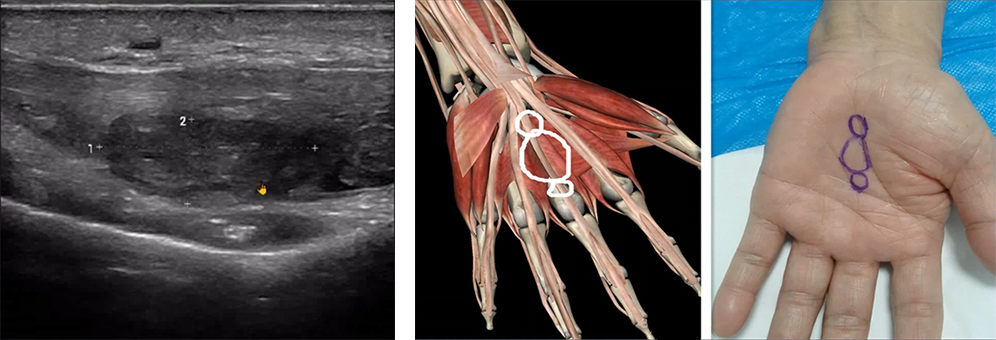

The patient experienced a noticeable snapping sensation in the wrist during active flexion of the interphalangeal joints.

?

Ultrasound detected a solid mass causing carpal tunnel syndrome.

This example showcases the role of POCUS in identifying and managing conditions like carpal tunnel syndrome, particularly in cases where traditional diagnostic methods might fall short.